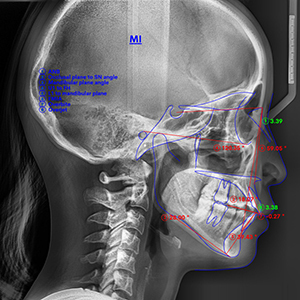

当院では、最新の口腔内スキャナーをを使用した歯並びのシミュレーションを無料でご提供しています。

これにより治療中の歯の動きや、矯正後の歯並びをイメージすることが可能です。

精密検査

(パノラマ・セファロ)